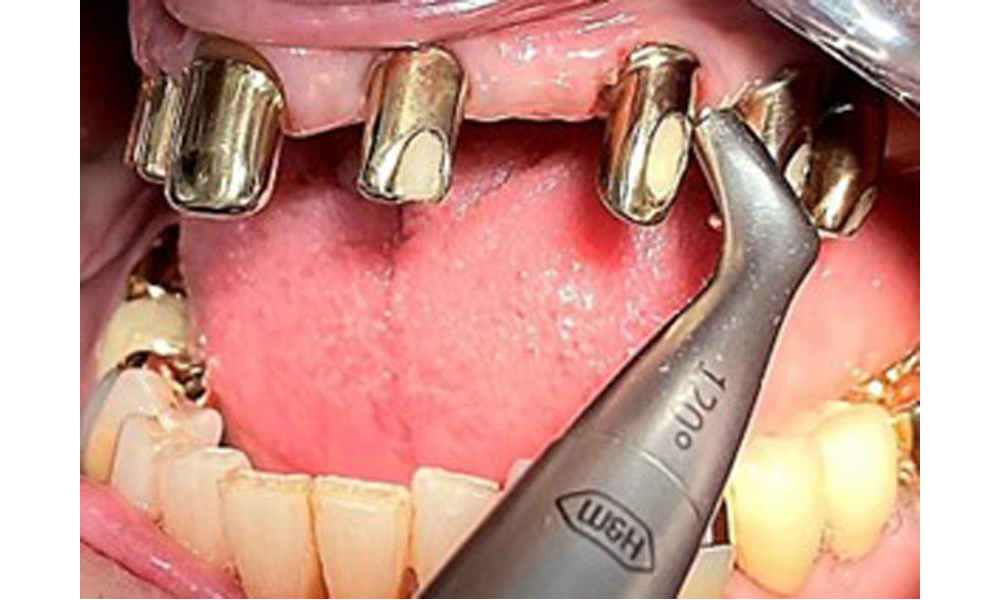

The patient was fitted with a combined removable maxillary telescopic prosthesis more than 25 years ago (Fig. 1, Fig. 2, Fig. 3) and is very happy with her dentures. The patient has an adequate fixed denture for the mandible (Fig. 4).

The dental findings are as follows: Combined removable implant and tooth-supported telescopic prostheses on implants 15, 13, 21, 23, 24, 25 and tooth 11 (Fig. 1, Fig. 2, Fig. 3). The patient was fitted with a fixed mandibular denture. Adequate bridges were present over 37 to 34 and 45 to 47 (Fig. 4), the crown margins were intact and there were no active caries. A composite filling with a marginal gap was present on tooth 43. There was mandibular gingival recession, exposing 1 to 3 mm of root surface. This also applies to 11.

Probing implant 23 at a probing depth of 4 mm using a plastic probe, showing negative BOP findings and a hyperplastic papilla.

Fig. 6: Probing implant 23 at a probing depth of 4 mm using a plastic probe, showing negative BOP findings and a hyperplastic papilla.

The periodontal status should be thoroughly examined once a year. This examination provides comprehensive documentation of the periodontal and implant findings, including pocket depths, periodontal recession and furcation involvement. This will ensure a rapid response to any potential progression of the mucositis, gingivitis, periodontitis or peri-implantitis. Implant probing using a plastic probe is recommended. In the present case, a mesial probing depth of 4 mm was detected mesial to implant 23. No suppuration or bleeding was detected, indicating the absence of peri-implantitis.